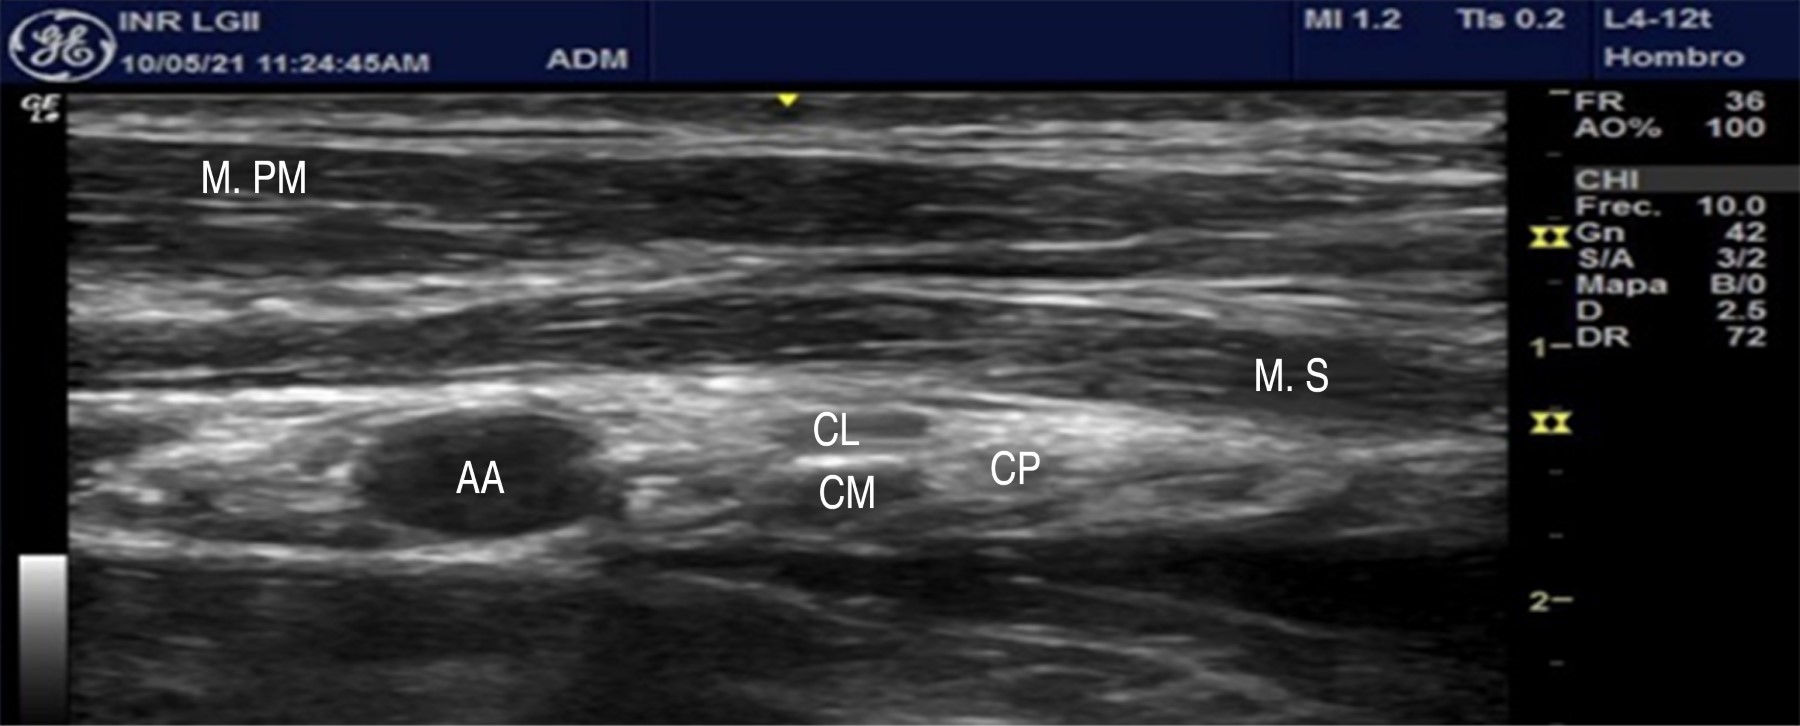

Respecto a la técnica descrita por Karmakar y colaboradores, el transductor se posiciona por debajo y paralelo a la clavícula, con inclinación craneal y medial al proceso coracoideo, lo que hace posible identificar, en el tercio superior, el músculo pectoral mayor seguido por el músculo subclavio. Medial a la imagen, en el tercio medio, la arteria axilar se visualiza como un halo circular pulsátil anecoico, con los cordones descansando sobre el músculo serrato anterior y los músculos intercostales, los cuales se encuentran por encima de la primera y segunda costilla superiores a la pleura y en disposición triangular laterales a la arteria axilar. Dichos cordones podrán observarse como halos hipoecoicos, rodeados de tejido hiperecoico con mayor anisotropía(16,17) (Figura 2).

Figura 2